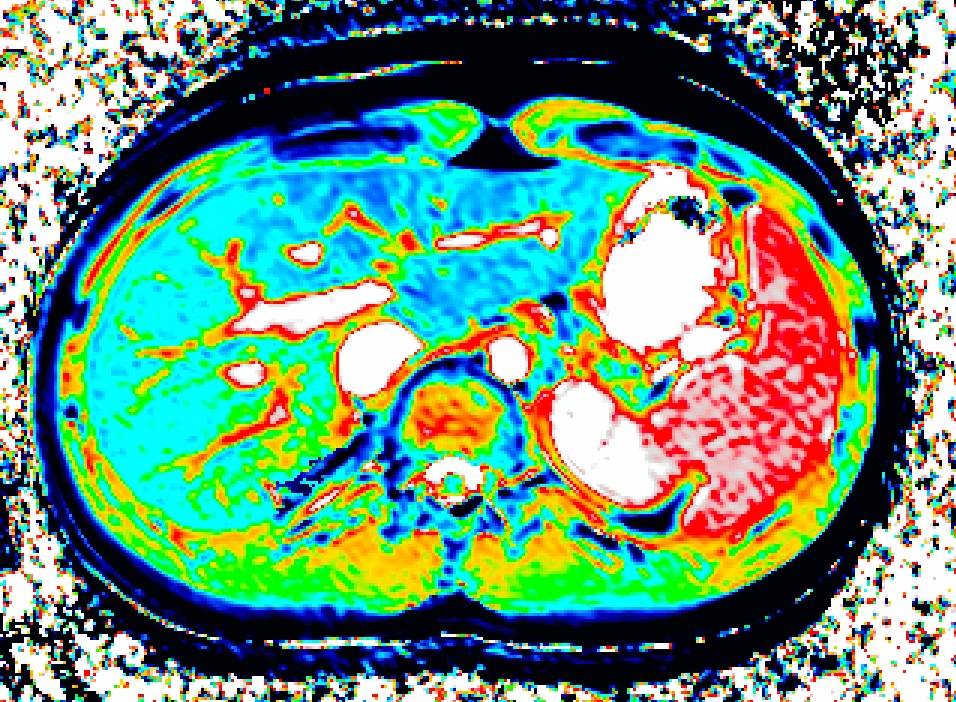

From study design to final reporting, Bioxydyn delivers repeatable MRI biomarkers that reveal tissue function, physiology and change. Our operational excellence and metrology help you compare results across sites, scanners and timepoints.

We're Bioxydyn - delivering quantitative MR biomarkers for pharmaceutical, biotech and academic studies. We combine scientifically leading methods with robust multi-centre study management and transparent analysis, turning complex images into repeatable measurements that support confident decisions.

Disease areas and services supporting quantitative MRI biomarkers across clinical trials.